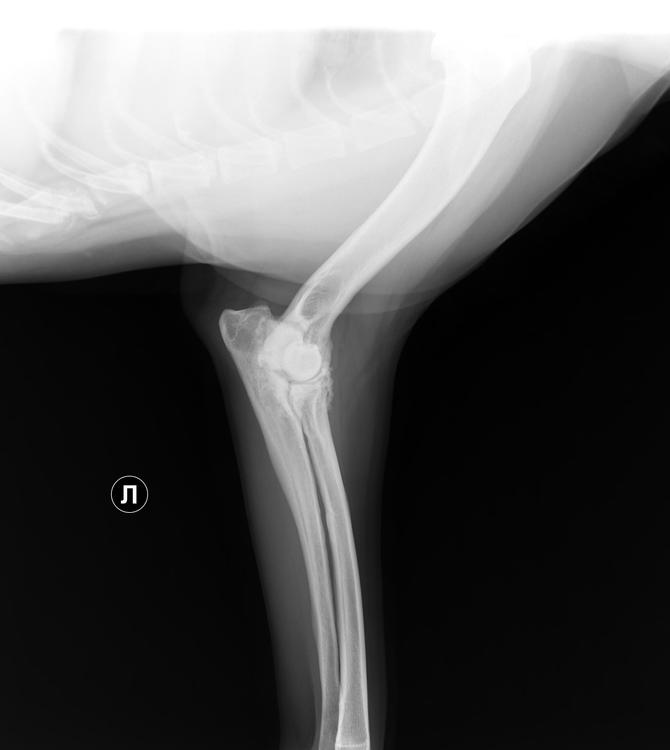

Бэкки Опубликовано 19 апреля, 2019 Опубликовано 19 апреля, 2019 Добрый день! Съездили вчера с Дусенькой к доктору, при осмотре доктор сказал, что до конца не сгибаются локтевые суставы, тазобедренные вопросов не вызвали, сделали рентген локтевых суставов и поясничного отдела. Результаты ниже. Снимки записаны на диск, но у меня нет дисковода)) Муж сможет днем на работе открыть и переслать мне, если нужны. Рекомендовано худеть и худеть на много, до 30 кг, а сейчас Дусенька 35,5 кг. , противовоспалительное пока не назначил, считает, что снижение веса значительно облегчит состояние, а пить лекарства еще успеем. Так что, будем много плавать, это нам можно, и мало кушать) 1 5